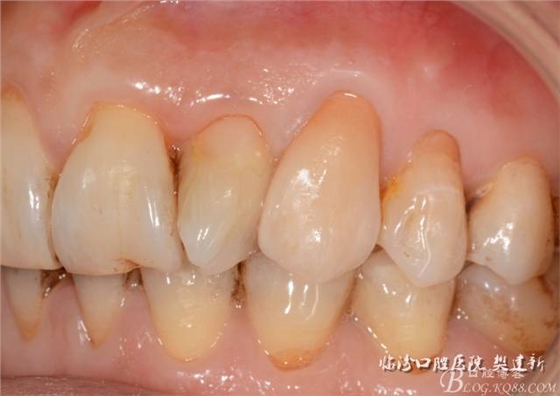

圖623代臨時冠口內(nèi)照

圖723備牙后模型照